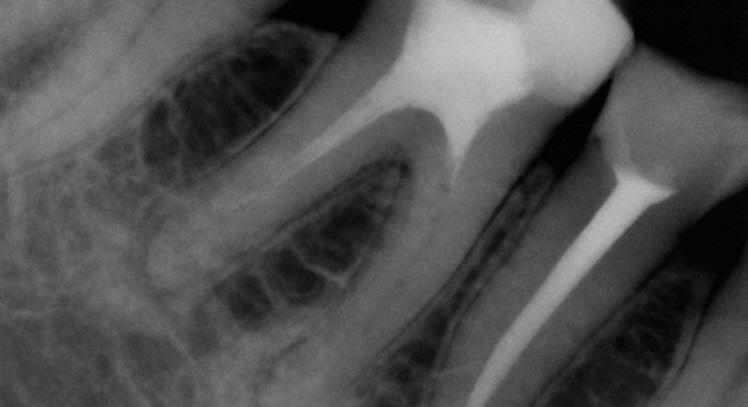

One of the suitable indications for FRC is the endodontically treated premolar with one big orifice and one large oval canal or deep furcation (Figs. 1-4). In such cases, an FRC can be placed as a Nayyar’s core modification5 without preparing the orifice part with Gates or Largos. The restoration can be finished as usual, directly with a conventional composite.

Fig. 1: Pre-operative situation with large orifice.

Fig. 2: A free space with a depth of 3-4 mm was created in the orifice part with a heated plugger.

Fig. 3: The proximal wall was created first using a conventional composite. The core was built up with everX Flow (GC), a flowable fibre-reinforced composite